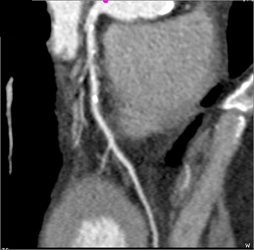

Diseased LAD